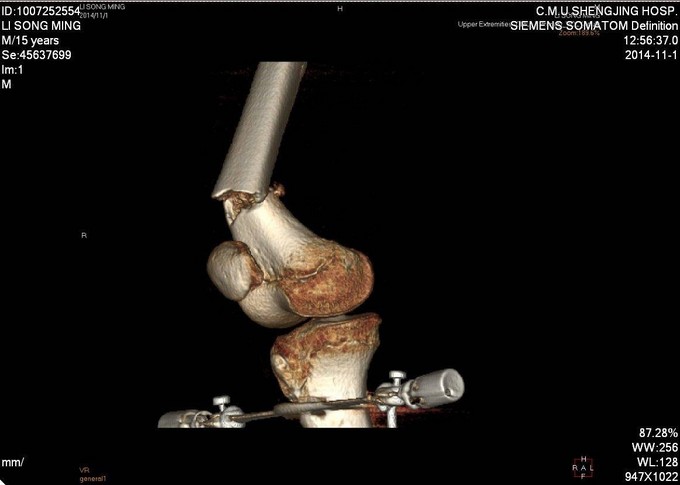

患者及家属自述于2014年10月31日,在学校与同学打闹过程中不慎别伤,伤后自觉右大腿疼痛伴有活动受限,就诊于当地医院行股骨正侧位X线片提示:右股骨远端骨折。未于治疗。后患者为求进一步诊治来我院急诊就诊,请我科会诊后,诊断为右股骨远端骨折,建议手术治疗,收入病房。伤来饮食、睡眠欠佳。大小便正常,体重无明显变化。

专科查体:见右大腿肿胀,畸形。大腿远端压痛阳性,轴向叩击痛阳性,可触及骨擦音,骨擦感。见双足高弓扬趾,右侧足背伸肌力5级,足背动脉可触及。

诊断:右股骨远端骨折 患者入院后急诊行生化检查等,查无手术禁忌症后急诊行右胫骨结节骨骼牵引术,维持患肢长度,减轻患者疼痛后,完善相关检查,请相关科室会诊后,查无明显手术禁忌症后行右股骨远端骨折闭合复位Liss钢板内固定术。